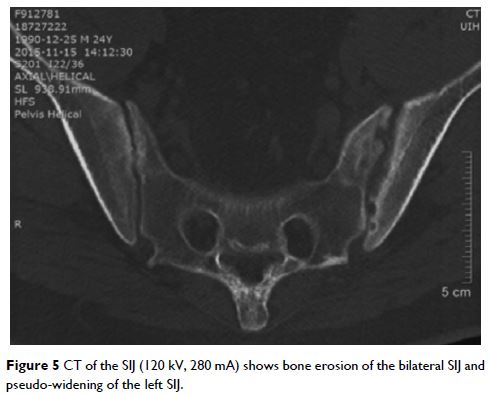

Case Series

- 作者:Wenji Chen, Yanyan Wang, Yan Li, Zheng Zhao, Lixia Feng, Jian Zhu, Jianglin Zhang, Feng Huang

- 期刊:Journal of Pain Research